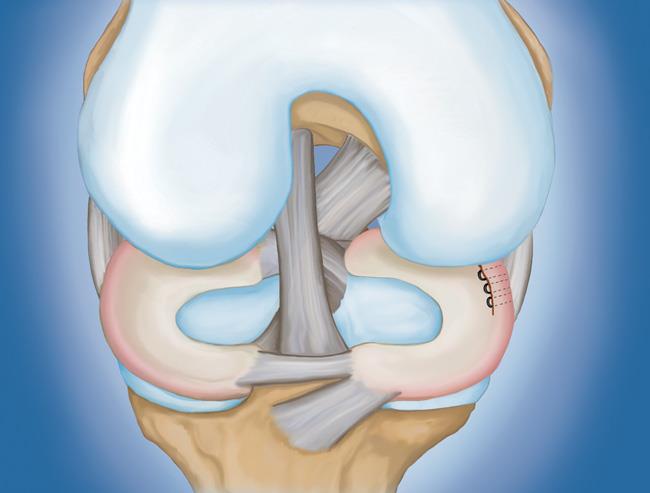

- 半月板修復。 一些半月板撕裂可以通過將撕裂的碎片縫合(縫合)在一起來修復。撕裂能否成功修復取決于撕裂的類型,以及受傷半月板的整體狀況。因為半月板必須一起愈合,修復的恢復時間比半月板切除術長。